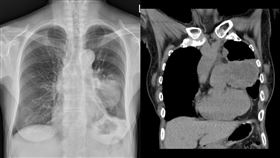

悚!40歲男不菸不酒 竟「癌末到處轉移」

肺癌是國人十大癌症中死亡率最高、新增人數最多的癌症。...